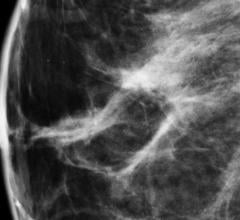

North Dakota Gov. Jack Dalrymple signed the Breast Density and Reporting Bill (HB 1370) into law April 9 in Bismarck, making North Dakota the 22nd state to enact such a law.